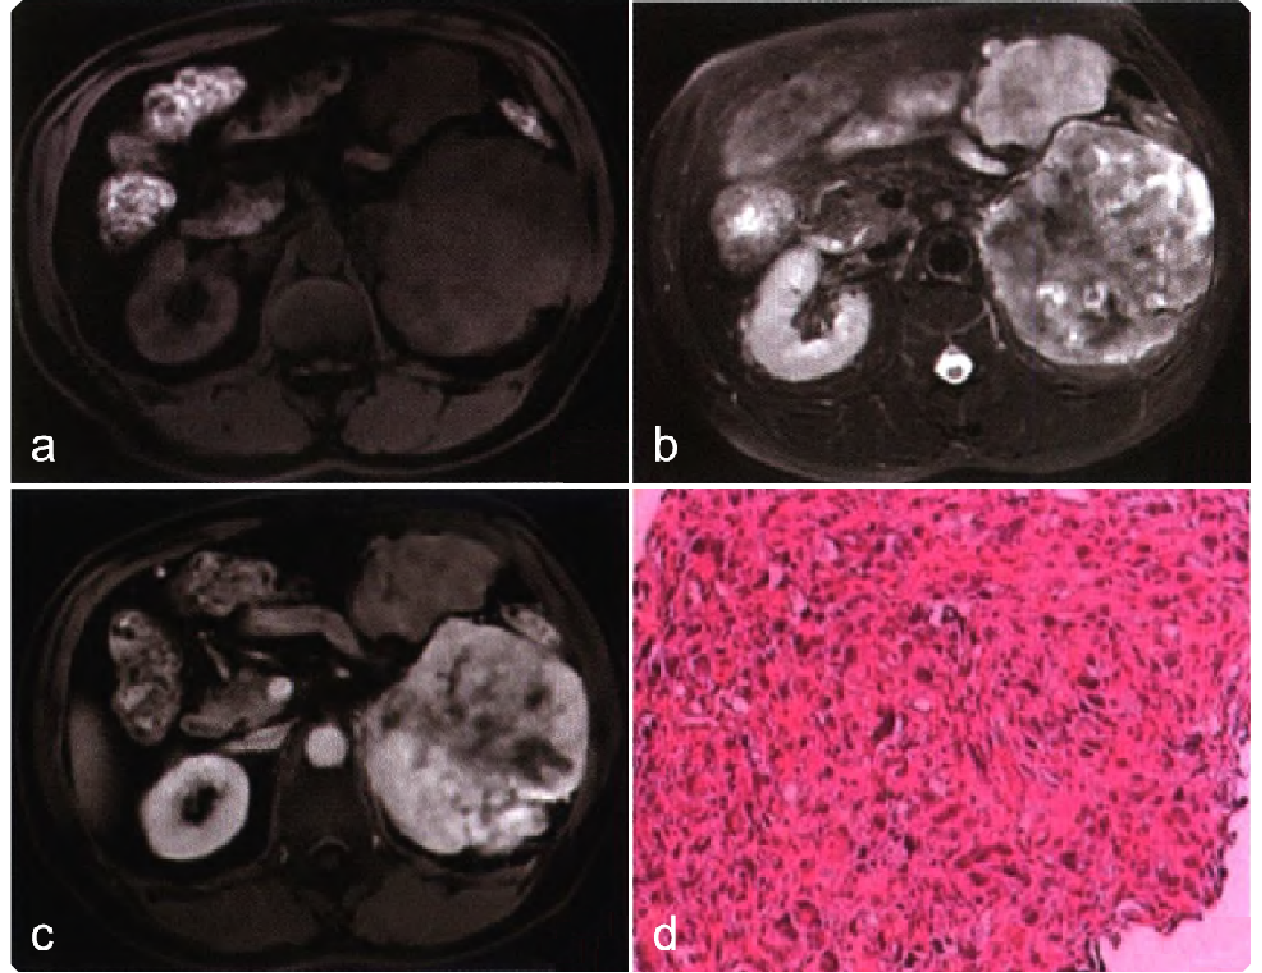

cc77276319006960e0db0009375aaf2d.png 病例 19:腹膜后多形性横纹肌肉瘤  60岁男性,因“左腰部肿块进行性增大1个月”人院。查体腰部无压痛,实验室检查无异常MRI平扫T1WI 肿块呈等-稍低信号(图a),T2WI呈不均匀明显高信号(图b),内可见囊变、坏死,未见出血;增强扫描肿块呈持续填充式强化,其内可见无强化区域(图c)。手术病理显示腹膜后肿物呈鱼肉样改变,质地较软,可见小出血灶及大片坏死;光镜下见肿瘤细胞弥漫分布,细胞大小不一,细胞核高度异型(图d)。免疫组织化学染色:SMA(+),Des(+),Myogenin(少许+),MyoD1(+),S-100(少许+),Ki-67(约30%+)。